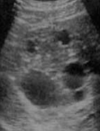

praziquantel and Albendazole

CE1 <5cm Albendazole >5 PAIR + albendazole